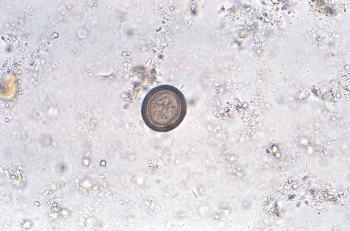

Medically Significant Fungi